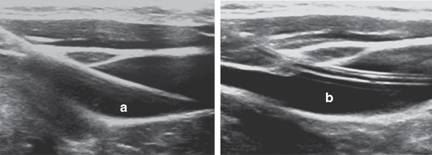

Figura 2: Corte longitudinal. a. Paso de guía a través de vena yugular interna. b. Catéter venoso central en luz de vena yugular interna.